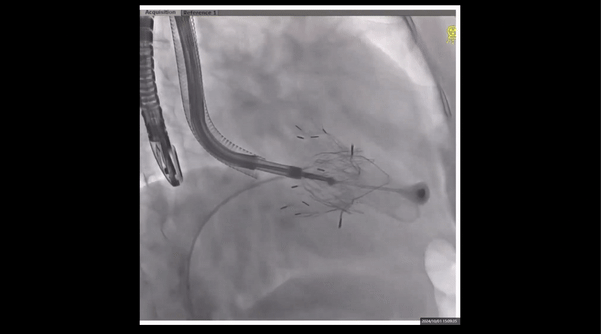

術前右室造影

夾持件位置確認

室間隔位置確認

術中經食道超聲輔助下可見LuX-Valve Plus夾持件抓捕瓣葉狀態良好,夾持件在位,室間隔錨定位置良好,假體瓣膜整體錨定狀態穩固。